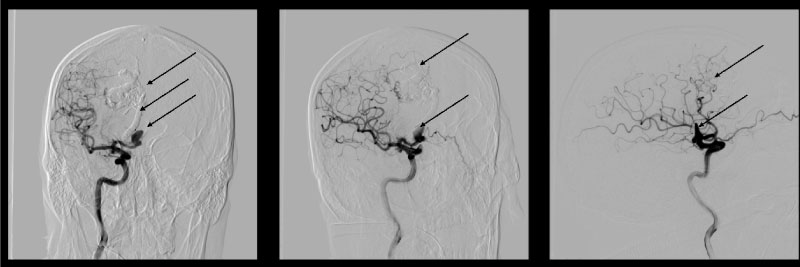

After a month, the patient underwent control cerebral angiography (Figure 8). We noted good angiographic and clinical results.

Figure 8: Cerebral angiography: AVM and aneurysm are not determined and the right recurrent artery of Heubner is normal. View Figure 8